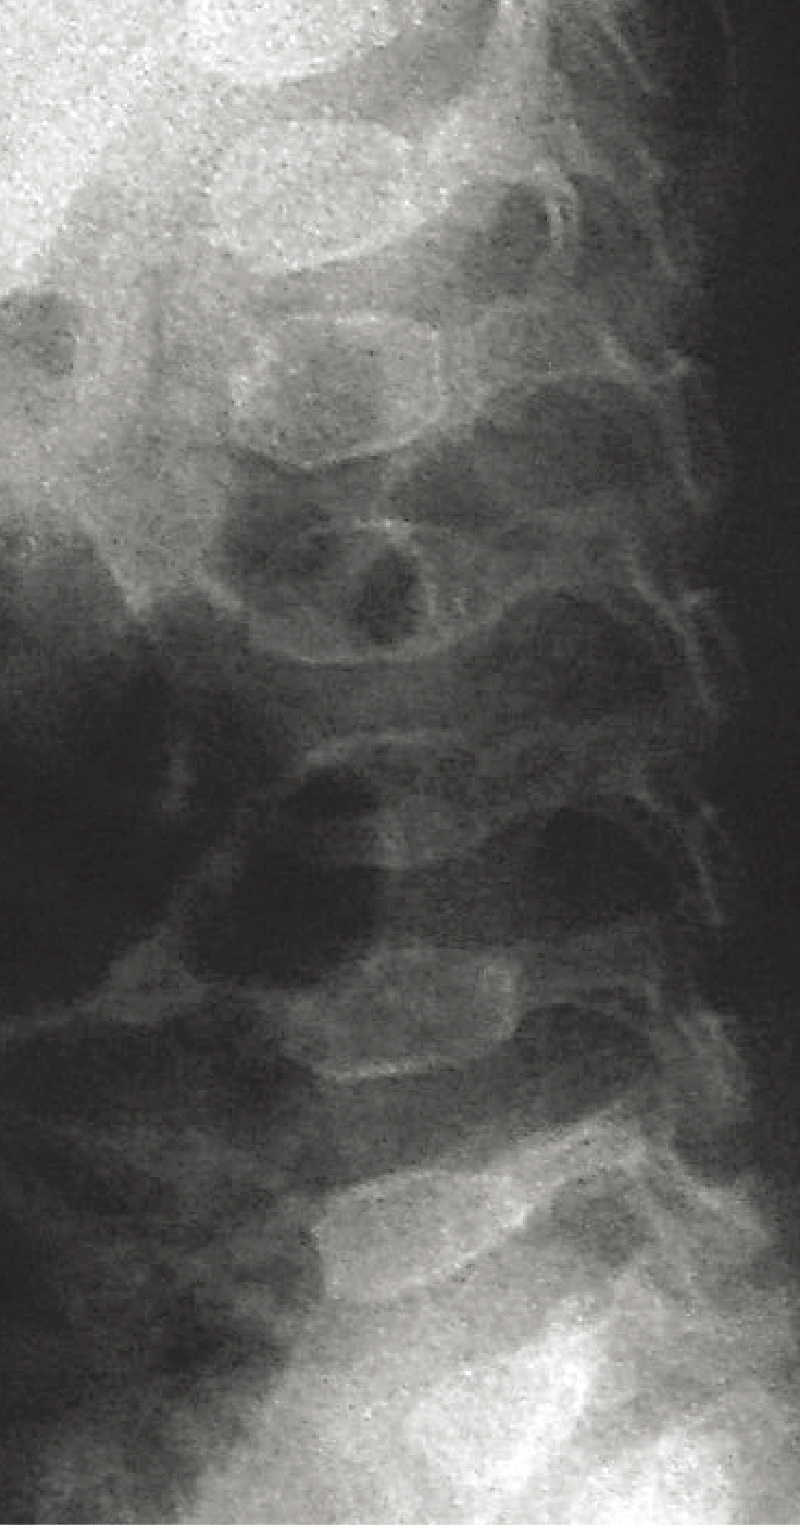

C. 脊椎側面像(2歳、女):椎体前縁が後縁より高い扁平椎が乳幼児期には特徴的である。